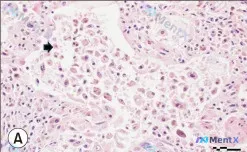

真皮浅层血管周红细胞外渗+含铁血黄素:第一眼先往肿瘤还是炎症靠?

整理到一份有争议的皮肤病理读片资料,先抛核心信息: > 病理描述:上真皮层,血管周围和毛囊周围可见红细胞外渗(标注a)、含铁血黄素细胞(标注b)。 之前的读片里还提到了「非典型细胞、核仁明显、浸润性生长、促结缔组织增生」,甚至倾向了恶性肿瘤方向。 但如果只看用户明确给出的核心描述——「上真皮层+血管...